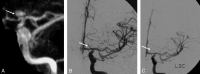

Background and purpose: Catheter angiography has been the criterion standard for follow-up evaluation of coiled intracranial aneurysms. In our center, CE-MRA has been used to evaluate aneurysm recanalization. Our aim was to investigate the feasibility and usefulness of a CE-MRA protocol for following patients with intracranial aneurysms treated with endovascular coiling.

Materials and methods: From September 2003 to December 2006, 134 aneurysms were treated by endovascular coiling in 124 patients by using detachable coils. These patients were followed with CE-MRA at 3 months, 15 months, and 3 and 5 years. MRAs were analyzed by 2 interventional neuroradiologists. Findings were assigned to 3 categories: complete obliteration (class 1), residual neck (class 2), and residual aneurysm (class 3).

Results: Initially, CE-MRA demonstrated 67 (50%) complete obliterations (class 1), 57 (41.79%) residual necks (class 2), and 8 (5.97%) residual aneurysms (class 3). No patient experienced rebleed during the follow-up period. A total of 214 patient-years of follow-up were obtained (range, 0-53 months). Two (1.49%) patients died after the follow-up, and 11 (8.21%) patients were lost to follow-up. On follow-up, 76 (56.72%) patients showed stable results. Fifty-six (41.79%) aneurysms showed change in their obliteration pattern. Of these 56, 47 demonstrated recanalization and 9 (6.72%) showed further obliteration. Most of the aneurysms that showed change in their obliteration remained stable on follow-up. Only 11 (8.21% of the total and 23.4% of those who showed recanalization) patients underwent recoiling or clipping.

Conclusions: CE-MRA can be used in routine practice to follow-up aneurysm recanalization noninvasively. CE-MRA permits close-interval follow-up and may show more filling of the aneurysm neck or sac than DSA.